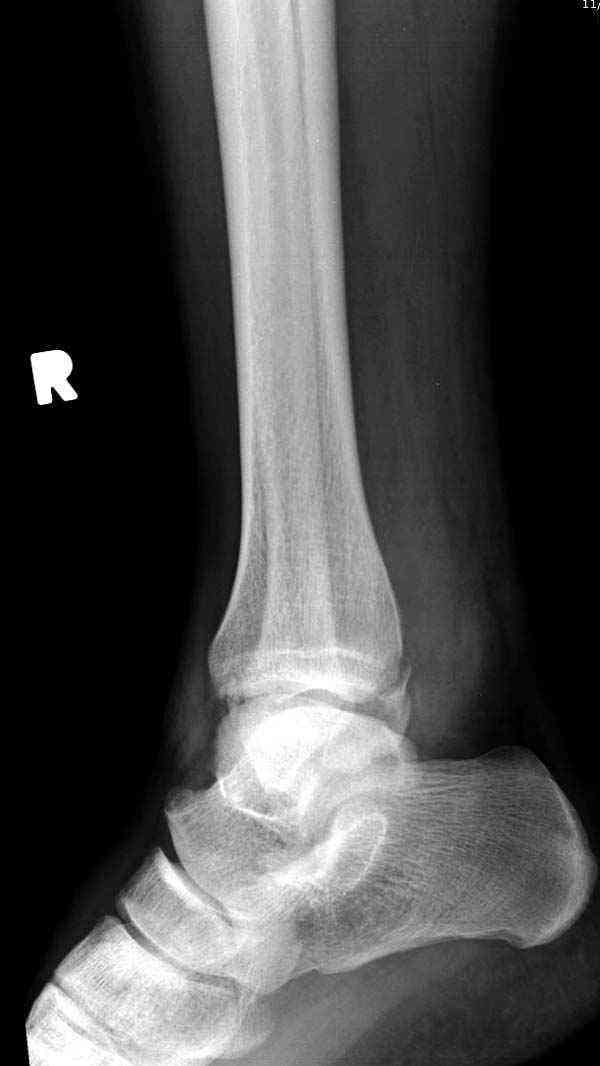

Нет первичных снимков, перелом очень низкий и под большим сомнением диагноз разрыва синдесмоза. Медиальная сторона отрепонирована на "хорошо" и, по-видимому, прорезание проволоки произошло во время операции. Без снимков трудно судить о высоте малоберцовой, а лодыжка находится в варусе. Лагирование получилось, но возле тонких шурупов передне-задний шуруп выглядит немного тяжеловато.

Медиальная лодыжка фиксируется каннюлированными лодыжечными шурупами перкутанно, а неточная репозиция (интерпозиция) является показанием к открытой технике. При больших вертикальных фрагментах нужны противоскользящие медиальные пластины.

Здесь несколько частных случаев: перелом голеностопа со сравнительными снимками и разрыв синдесмоза, а также медиальная Hook пластина.